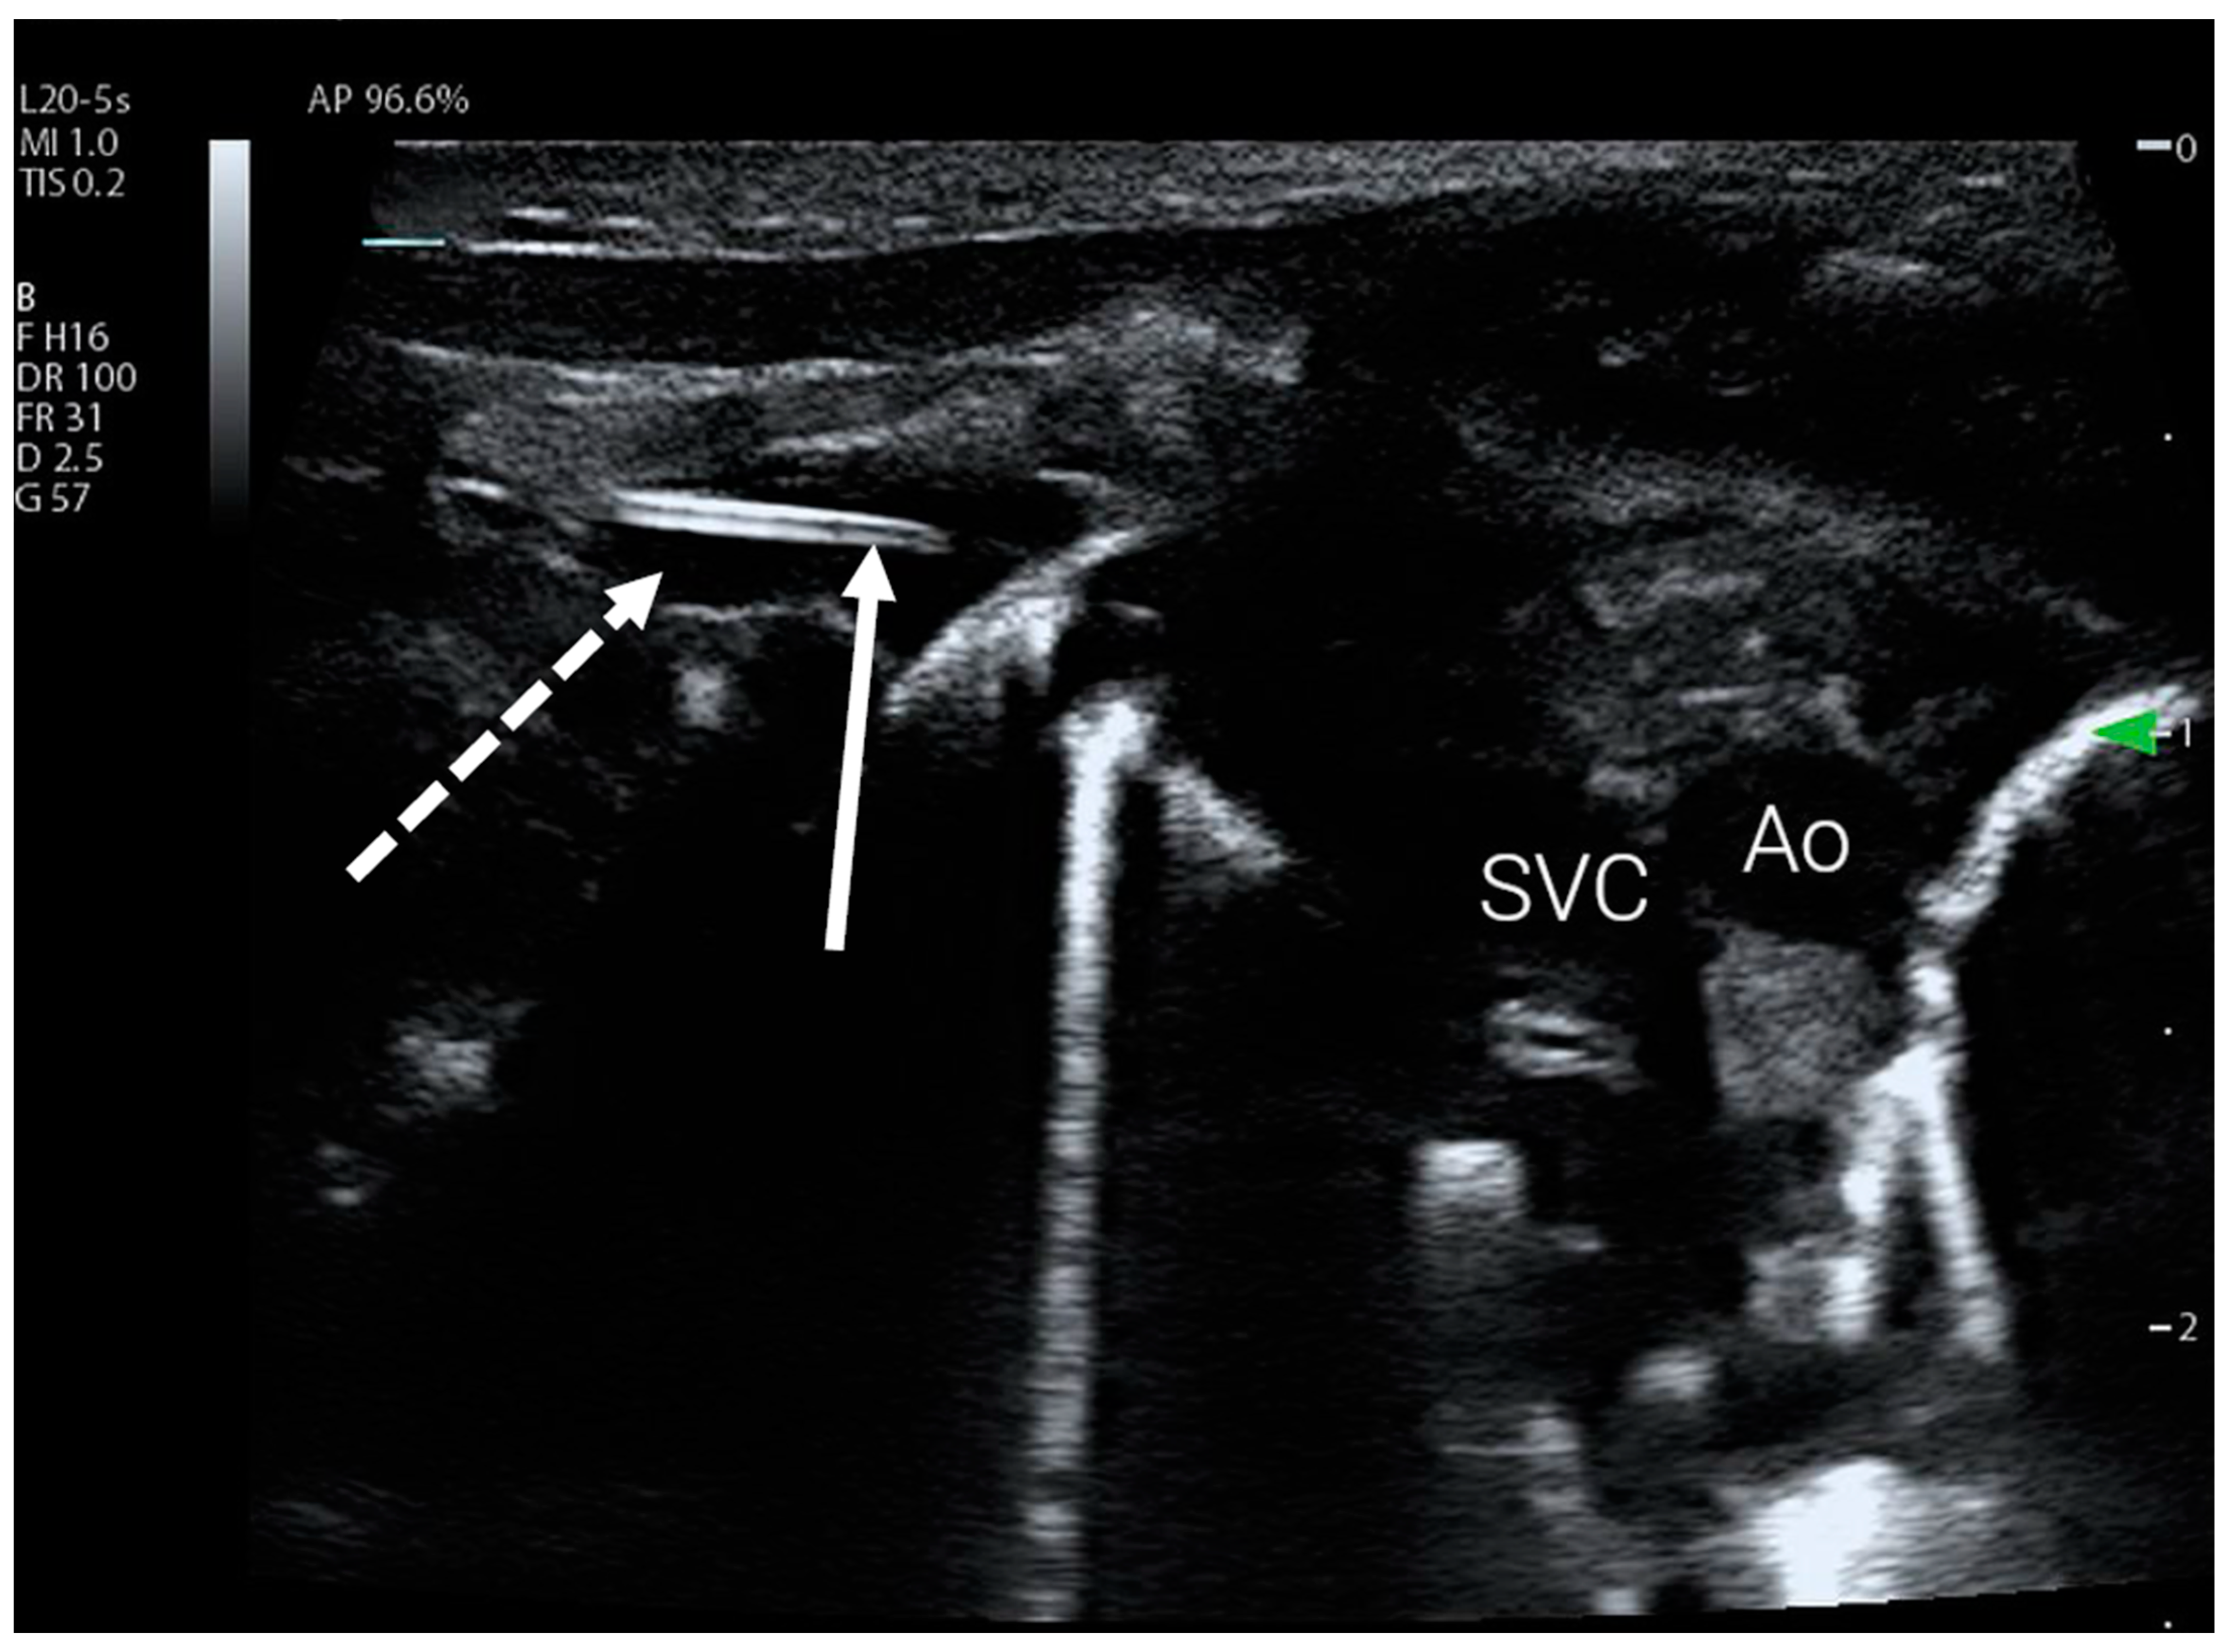

Figure 1.

PICC catheter clearly visible in the inferior vena cava (IVC) using a simple lateral abdominal view. The catheter is marked with a dotted arrow, and the full arrow indicates its tip.